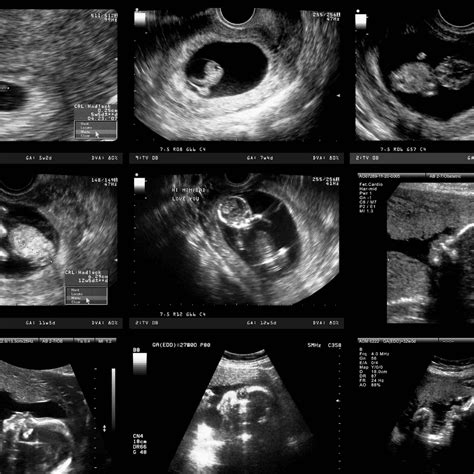

A 9 weeks pregnant ultrasound is typically performed to assess the baby's growth and development. At this stage, the ultrasound can provide detailed images of the fetus, allowing healthcare providers to measure the baby's size, check for a heartbeat, and evaluate the overall health of the pregnancy. This scan is usually done transabdominally, meaning the ultrasound probe is moved over your belly, or transvaginally, where the probe is inserted into the vagina for a clearer view.

At 9 weeks, your baby is undergoing rapid development. Some of the key milestones include:

• Size: Your baby is about the size of a grape, measuring approximately 0.63 inches (1.6 centimeters) in length and weighing around 0.07 ounces (2 grams).

• Heartbeat: The baby's heartbeat is usually detectable by ultrasound, and it may be visible as a rapid fluttering.

• Organs and Systems: Major organs and systems, such as the brain, heart, and lungs, are beginning to form. The tail, which is a normal part of early development, is also visible.

• Limbs: The baby's arms and legs are becoming more defined, with small buds that will eventually develop into hands and feet.

• Facial Features: The eyes and ears are starting to take shape, and the mouth and tongue are forming.

• Gestational Sac: A fluid-filled structure that contains the embryo.

• Yolk Sac: A small structure that produces blood cells and helps in the early development of the embryo.

• Embryo: The developing fetus, which should be visible and measurable.

• Heartbeat: A detectable heartbeat, which is a positive sign of a healthy pregnancy.

• Crown-Rump Length (CRL): The measurement from the top of the head to the bottom of the buttocks, which helps to estimate the baby's age and growth.